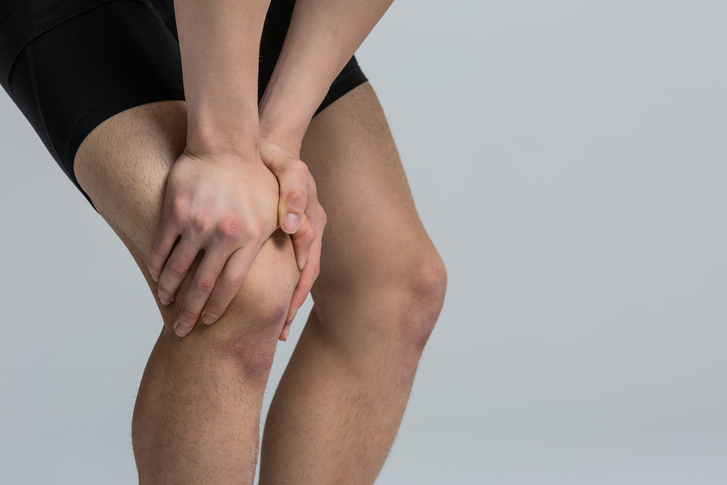

무릎 연골 손상 증상들은 망가진 연골 부위의 염증 반응때문에 반복적으로 붓기도하며 오랜시간동안 한자세로 앉아 있다가 나타날 때 관절이 굳어진것같은 느낌과 무릎이 구부러지거나 펴지지 않다가 급격히 움직이기도 한다고 해요.

뼈랑 뼈 사이에는 연골이 있어요. 연골이 망가진다는 소리는 뼈랑 뼈가 바로 닫게 된다는 소리 이라고 합니다. 그러면 통증이 발생하게 되죠. 무릎을 움직일 때 마다 통증이 생기고 불편해져요. 무릎 운동이 뻐근해지고 힘들어져요.

무릎 연골 손상의 증상은 대략적으로 과도한 손상이 있은 후에 통증을 느끼게 돼요. 계단을 오르내리거나 쪼그려 앉을 때 무릎에 통증이 느껴지거나, 약간만 걸어도 무릎이 수시로 붓고 뻣뻣한 느낌이 든다면 이것은 무릎 연골 손상 증상으로 볼 수 있어요. 간혹 관절에서 소리가 나기도 하며, 심하게되면 무릎을 완전히 펴지 못하는 증상이 발생하게 돼요.